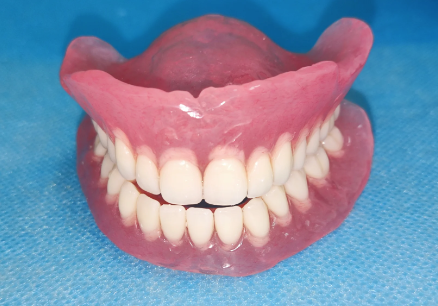

活动义齿一般多少钱一颗费用?2026年最新价格揭秘! 文章揭秘2026年活动义齿最新价格。通常镶活动假牙一颗1000 - 3000元,不同类型费用有别。如隐形义齿1000 - 1200元,便宜但寿命短、咀嚼差;钴铬合金等1500 - 2000元,强度好、使用久;纯钛基托2000 - 3000元,舒适美观。此外,地区、医院等级和医生水平也影响价格,选义齿要综合考量。 活动义齿 2026年03月04日 0 点赞 0 评论 7 浏览

活动义齿哪种最舒服还不伤害基牙?揭秘3种最佳选择! 本文围绕“活动义齿哪种最舒服还不伤害基牙”展开。首先强调了活动义齿舒适与护基牙的重要性,接着介绍了纯钛金属基托活动义齿等三种义齿的特点,包括舒适度、对基牙的影响、价格等。还给出选择建议,要考虑口腔状况、经济因素,并听取医生建议。最后提醒佩戴后注意适应期、清洁和饮食,综合考量选适合自己的义齿。 活动义齿 2026年03月04日 0 点赞 0 评论 12 浏览

补一颗活动义齿多少钱?揭秘真实费用与选择技巧! 本文围绕补一颗活动义齿的费用及选择技巧展开。费用大致在100 - 300元,受材料、修复难易、医院级别、当地经济等因素影响。不同材料义齿各有特点和价格区间。选择时要综合自身情况,选正规机构,多对比。此外,后期维护有成本,需正确佩戴清洁。提醒大家综合考量价格、质量和舒适度,必要时咨询医生。 活动义齿 2026年03月04日 0 点赞 0 评论 7 浏览